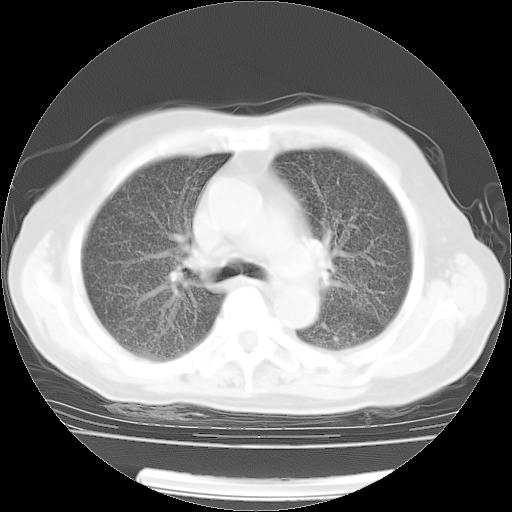

肺部CT平扫未见异常。

4月14日肺部CT